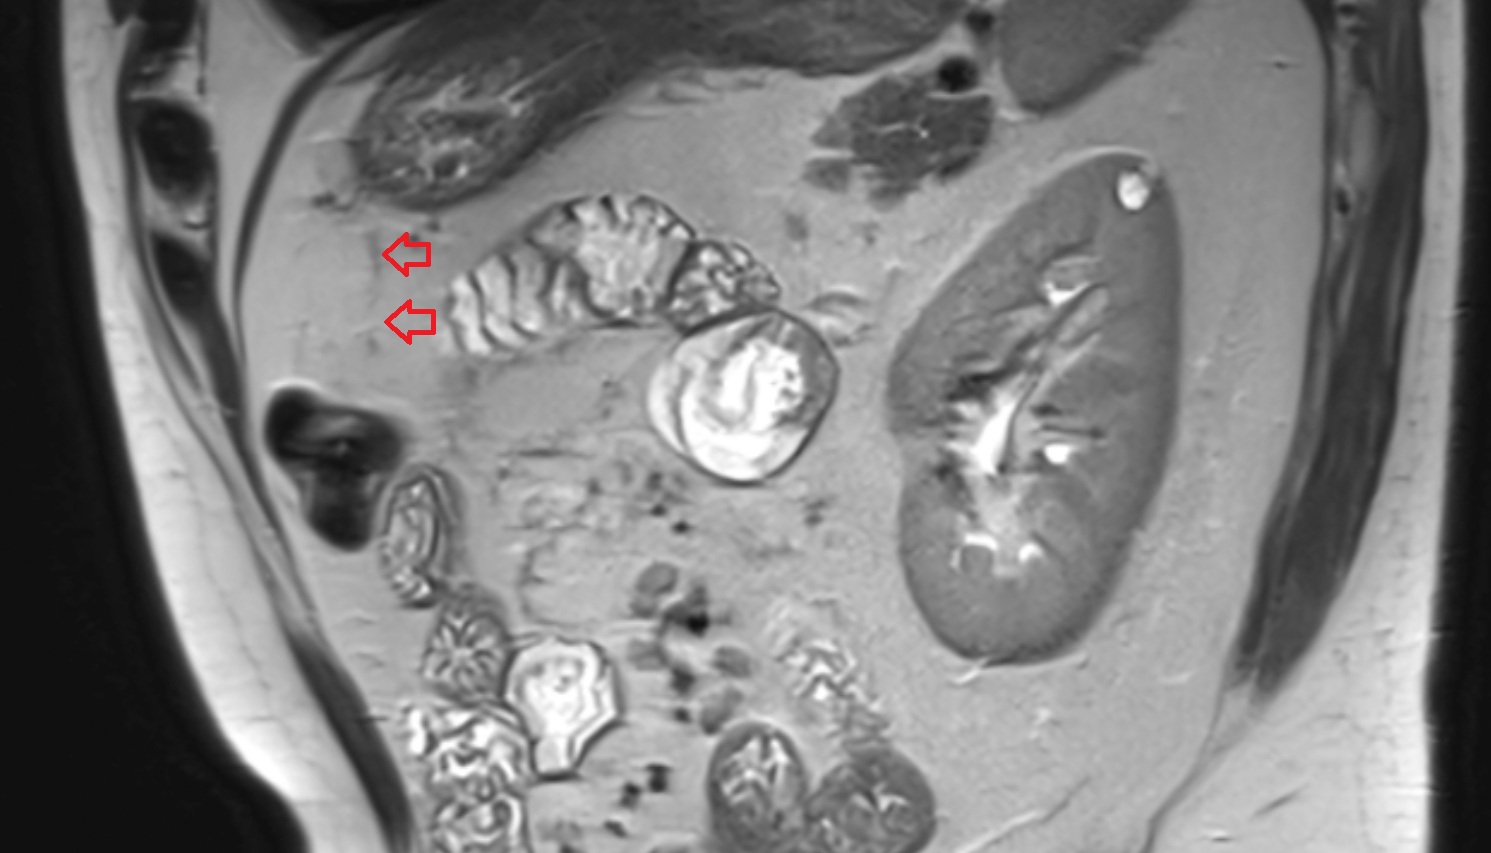

- Placenta

- Uterus (pregnancy)

- Amniotic fluid

- Maternal ovaries